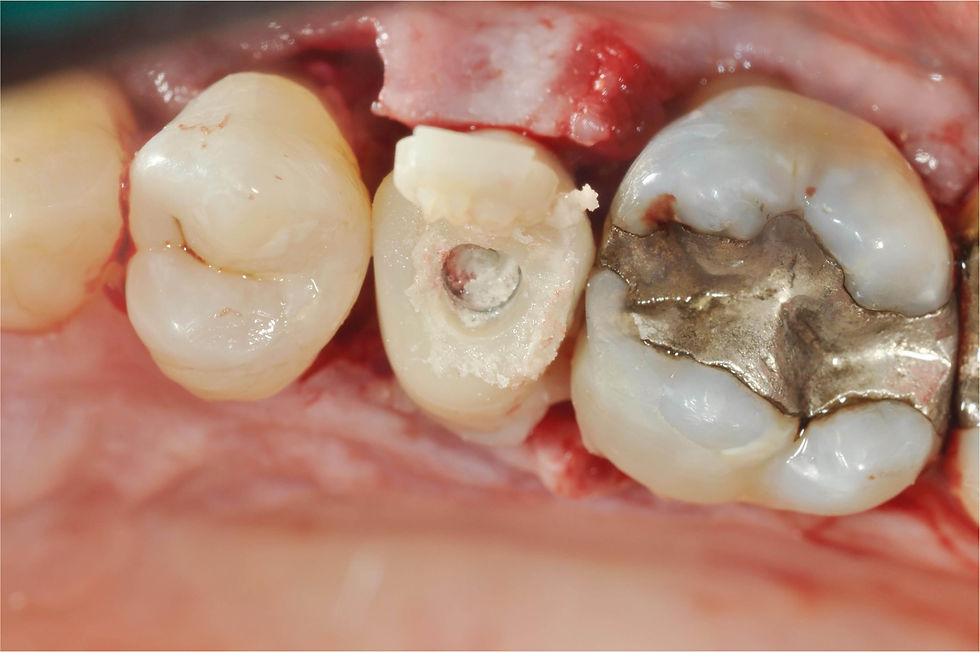

Adjustment of the temporary abutment before relining a pre-made temporary prosthesis prepared by the laboratory.

Aspect of the temporary prosthesis.